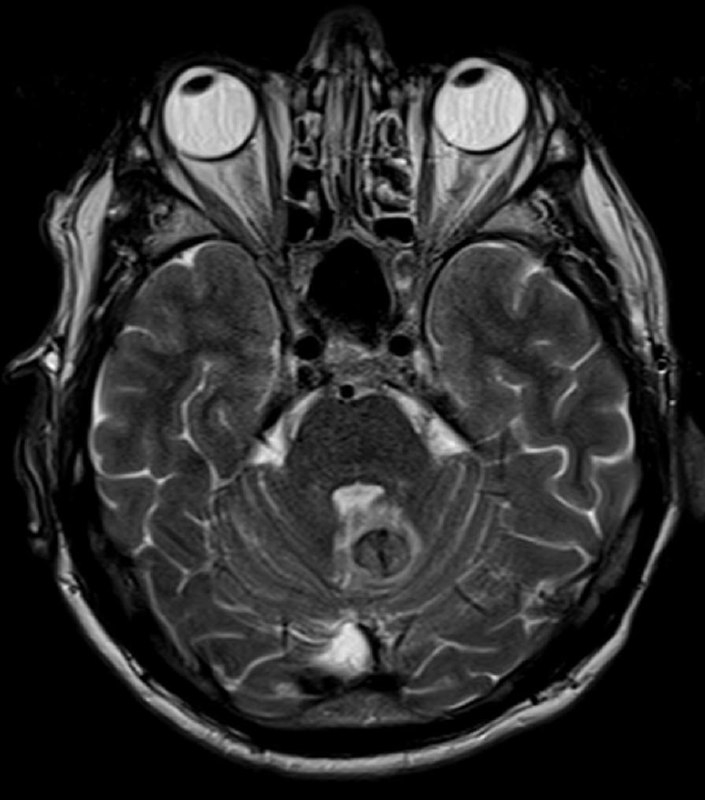

в декабре 2020 удалена менингиома, а теперь - вот так